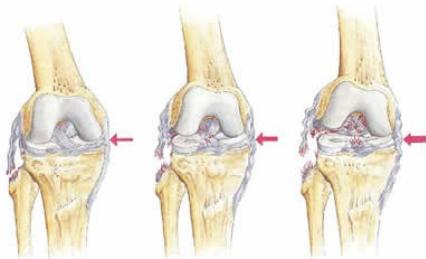

Medial Collateral Ligament (MCL) Injury

Mechanism:

- Valgus stress to the knee

- Most commonly occurs at medial femoral attachment

Lateral Collateral Ligament (LCL) Injury

Characteristics:

- Isolated LCL injuries are uncommon

- Treatment: Conservative management with brace if grade II

Complete tears with associated ACL/PCL require reconstruction